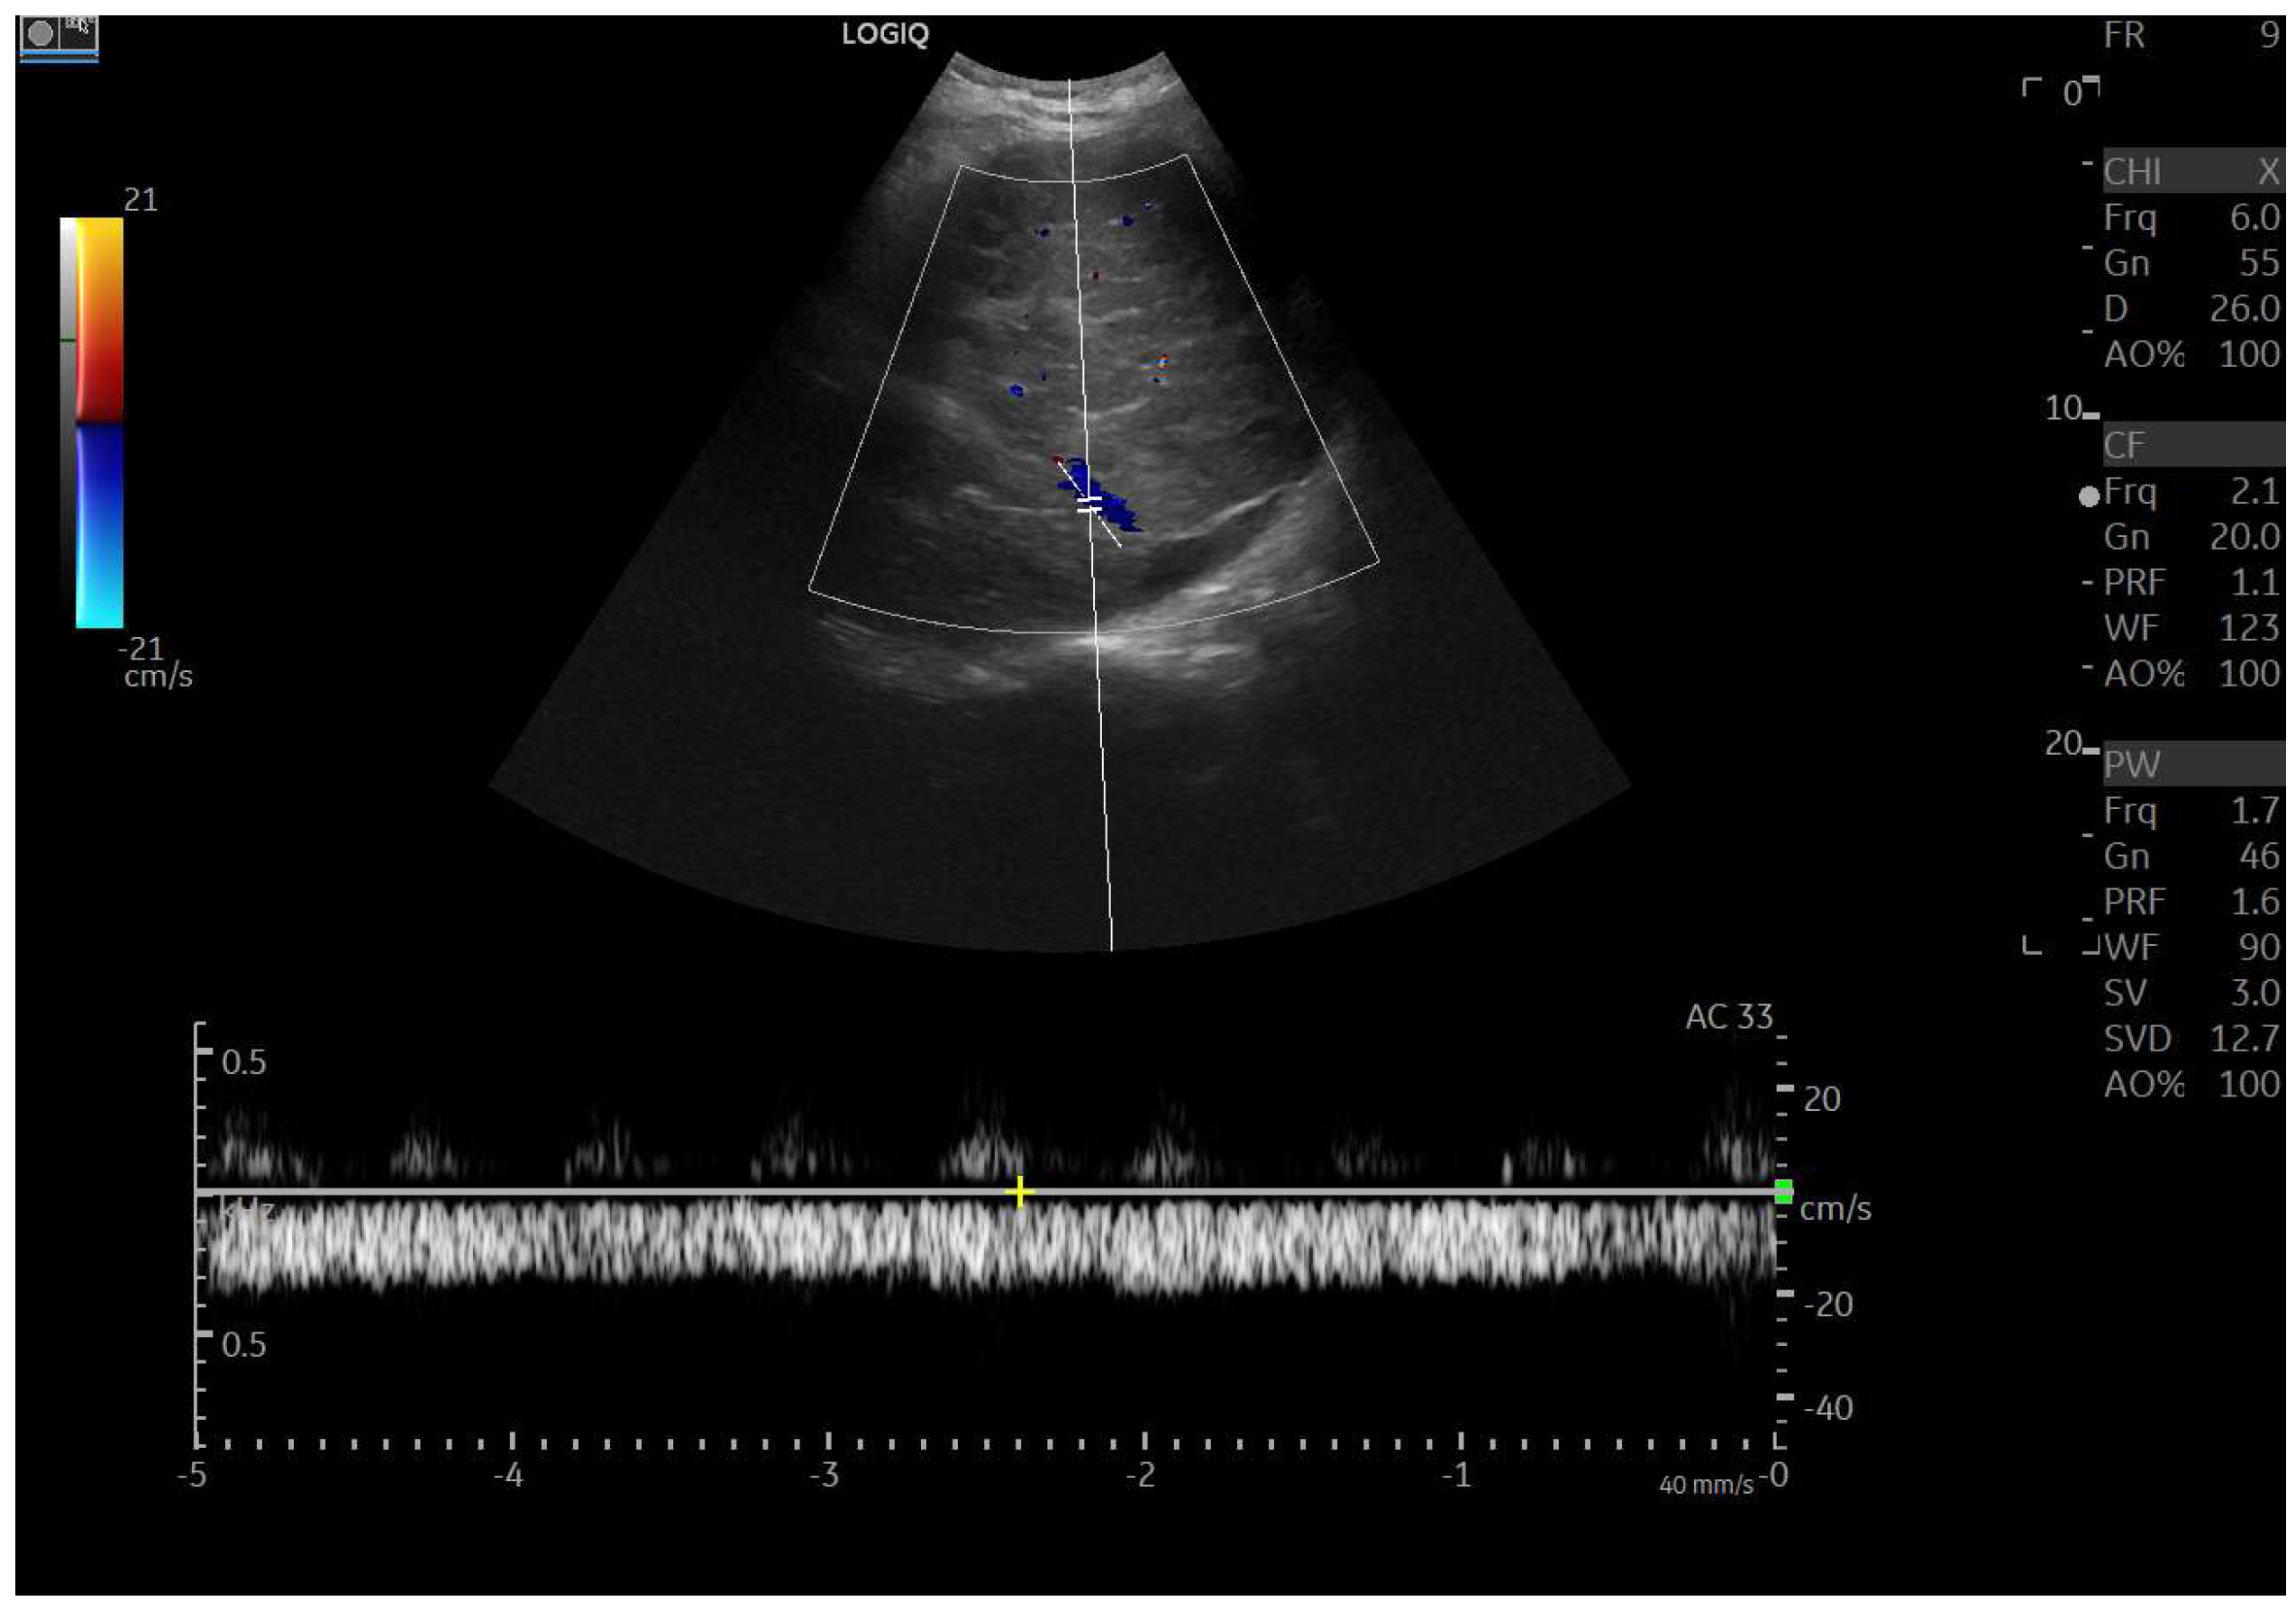

CEUS is valuable for characterizing the contrast enhancement patterns of liver nodules [68,69,70,71]. In Europe, the US contrast agent SonoVue® (sulfur hexafluoride; Bracco, Milan, Italy) is approved only for intravenous applications in patients over 18 years of age [72]. CEUS use in Fontan patients remains limited due to their frequent collateral circulation with right-to-left shunts, which is considered a contraindication in Europe but not in the United States. Beyond structural liver changes, CEUS reveals markedly heterogeneous hepatic enhancement with mosaic or reticular patterns, mainly due to slow and reduced enhancement near congested hepatic veins—one of the most common imaging features of FALD [54,73]. Anecdotal experience suggests that CEUS demonstrates heterogeneous and decreased liver enhancement in the portal venous phase, similar to cirrhosis of other etiologies (Figure 14, Figure 15). Abnormal enhancement is more prominent at the liver periphery than centrally, while the hypertrophic caudate lobe often shows more homogeneous enhancement. In patients with FALD, the altered hemodynamics resulting from chronic hepatic venous congestion and low cardiac output can significantly influence CEUS dynamics. Despite these circulatory changes, CEUS in FALD generally preserves the standard temporal enhancement pattern. The hepatic veins, although congested, do not typically show early enhancement, as microbubble distribution primarily reflects arterial input. The systemic hypokinetic circulation characteristic of FALD may lead to delayed arterial arrival times and a prolonged transit of contrast, especially in the background of the liver. Nonetheless, FNH-like nodules frequently exhibit intense and early arterial-phase hyperenhancement, suggesting preserved or increased arterial supply in these lesions. This contrast behavior is essential for lesion characterization.

Figure 14.

Contrast-enhanced ultrasound (CEUS) in the late phase shows the appearance of hypo-vascular areas due to varying degrees of congestion and hepatic alteration. These areas may mimic malignant nodular lesions with early washout.

Figure 15.

CEUS exam showing late heterogeneous enhancement in the arterial phase with evidence of hypo-enhanced areas, thus mimicking a malignant wash-out.

CEUS plays a crucial role in evaluating hepatic nodules in FALD and Figure 16 (Figure 17). In non-cardiac cirrhosis, contrast washout in the late phase is highly indicative of HCC. However, in FALD and other congestive hepatopathies like Budd–Chiari syndrome, FNH-like nodules can also exhibit delayed washout, leading to false positives if the LI-RADS system is strictly applied [74]. An FNH-like lesion is a benign hyper-vascular regenerative nodule that mimics focal nodular hyperplasia on imaging but arises secondary to chronic hepatic venous congestion and altered perfusion, typically occurring in FALD or other forms of congestive hepatopathy. Washout in the portal venous phase, in contrast, is uncommon in FNH-like nodules and more specific for HCC [69]. Despite limitations, ancillary LI-RADS criteria and portal venous phase washout remain useful for identifying potentially malignant lesions [75,76].